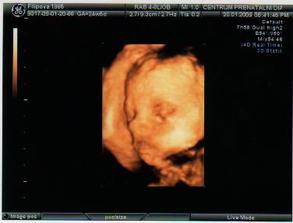

22.12.2008- velký UTZ v Centru Prenatální Diagnostiky na Veveří, vše je v pořádku, poprvé se mnou byl i manžel. Čekáme HOLČIČKU.

Pod stomeček jsme dostali i první pohyby